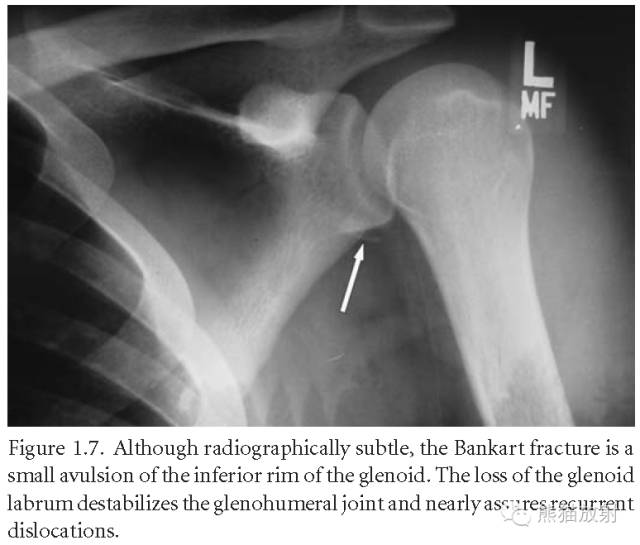

Bankart骨折(前下盂唇撕脱骨折)。关节盂上唇缺失会使盂肱关节不稳定,导致关节脱位反复发生。